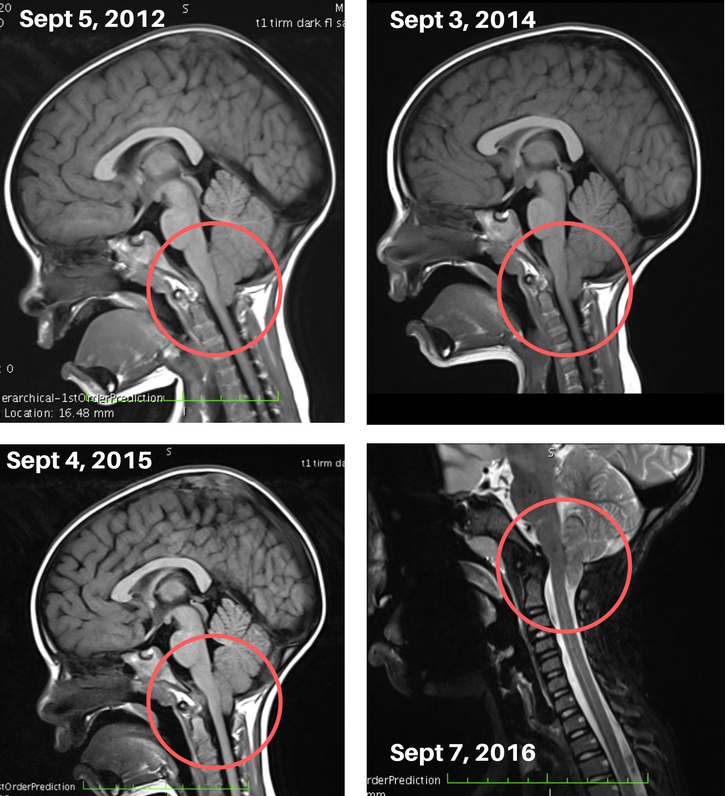

Okay so let me get into some imaging to show you what Henley’s brain actually looks like. Below are pictures of Henley’s brain AFTER her first surgery in 2012 when she was 2 years old. Each year I went in to our local neurosurgeon telling him that while yes, she had stopped vomiting every single day and a few things had certainly improved, we still felt like there were some issues but weren’t sure what to attribute to. We went year after year with basically the same response. β€œThese things aren’t Chiari related”. It made me feel defeated and like I was crazy.

In 2016, I knew in my gut that something was not right. So I set out for a second opinion and wanted to find the most knowledgable person I could in the world of Chiari to talk to. We met with tons of professionals, had sleep studies, swallow studies, speech and occupational therapy evaluations, MRIs, CT scans, X Rays and ended up in New York sitting in front of Dr. Greenfield in December of 2016. All of our speculations of this actually being β€œChiari related” were validated and surgery was scheduled for a few months later. Here is a before and after video of what Henley’s brain looked like pre-and post op in March 2017.

Sunday morning we sat and talked a little bit about it all and I felt like this was the first time she maybe understood WHY this was all happening. I forget that sometimes when she is being tested for things and we are investigating a specific issue we ask a lot of placebo questions to mask the real questions we need answers to. For instance, instead of asking questions that may lead her into an answer like "Does your head hurt?" We will look at a pain scale and say things like "can you tell me how you arm feels?, your eyes? your head? your elbows? etc" This way she doesn't really know why we are asking and she won't mask her true answer. Because of this she maybe doesn't know the RESULTS of what we found out and what has led us from one step to another. News Flash: She doesn't read the CaringBridge. All she knows is whatever she said and we found out is now the reason she is having this super scary operation. I figured that maybe sharing this info with her is the info she needs to be able to process through what is about to happen. It's also very important to me that she knows that we are doing this FOR her and not TO her and that Adam and I are her warriors and we are fighting with her on the same team, with the same goal. I pulled out her MRI images from the last 5 years and showed her the comparison. I explained the images to her as best I could and told her that her brain was having a hard time "breathing" {translation: Very little spinal fluid is able to get through} and that her brain was so tight in there and this part of her brain needed a little more space so that it didn't feel so squished by its neighbors {translation: Her brain stem is being compressed by the cerebellum and anterior craniocervical junction (CCJ) and needs more room to function properly} So Dr. Greenfield is going to go in and give the brain some more space so that it's happy and no one is squishing each other.